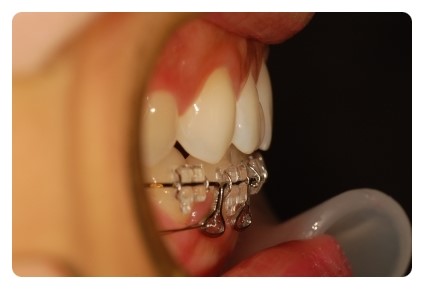

혹시 제 치아교정후기를 처음보시는 분들은 스크류가 웨 삐뚤게 되어잇나 이상하게 생각하실텐데

가운데 자리에 스크류를 심엇다가 너무 아파서 빼고 옆으로 빗겨서 다시 심엇어요

그바람에 스크류에 거는 고무줄도 한쪽은 체인3개, 다른한쪽은 4개로 당기는힘을 다르게해요